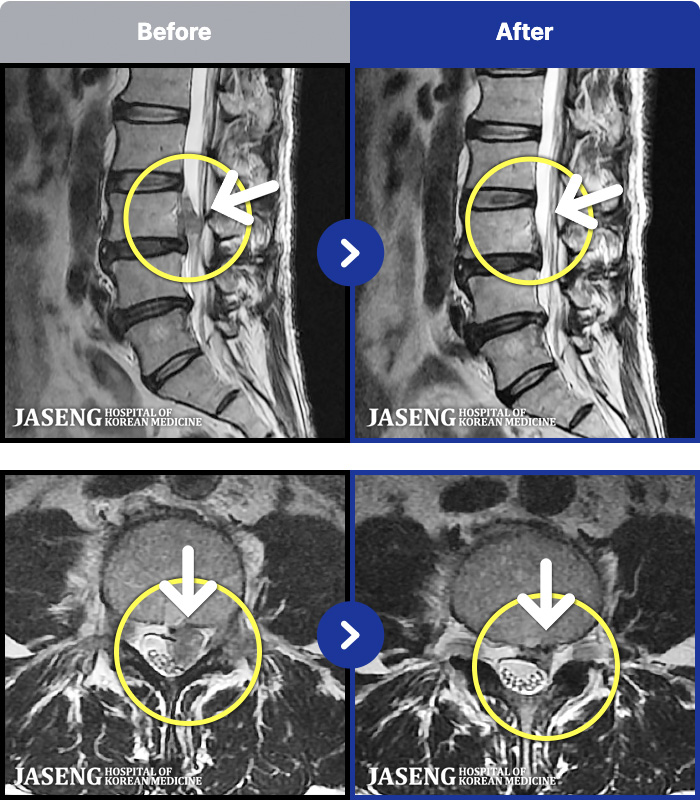

101 MRI ũ ʸ Ȯϼ.

㸮 ϻ .

[Ȼ] 23.03.13~24.05.08

[õ_㸮ũ] Ǫ ݺ ؽ Ͽ

No.101

ȸ 29,428

[õ_㸮ũ] ö ݺ ؽ Ͽ

No.100